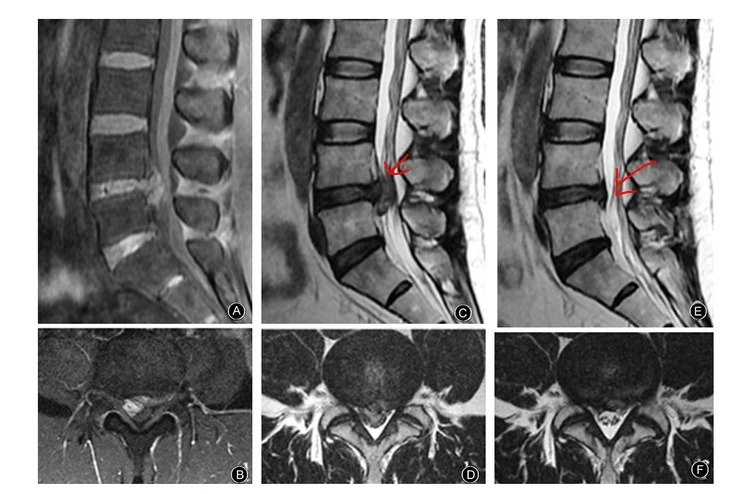

이 논문 영상은 극심한 요통과 하지통을 호소했던 48세 남환의 사진입니다. 초기 SLR은 좌측 하지 60도 우측 하지 10도 정도였으며 약 2030mm3 정도 였습니다. 그런데 4달이 지나자 SLR은 모두 회복되었으며, 최종 MRI 재검사에서는 통증은 모두 사라졌고 디스크는 대부분 흡수된 상태였습니다.